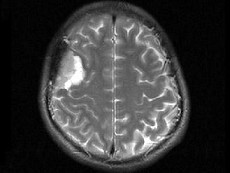

男,48岁,发作性口角抽搐半月,根据所提供图像,最可能的诊断是()

男,48岁,发作性口角抽搐半月,根据所提供图像,最可能的诊断是()

[单选题]男,48岁,发作性口角抽搐半月,根据所提供图像,最可能的诊断是()A . 右额叶胶质瘤B . 右额叶非典型脑膜瘤C . 右额叶骨瘤D . 右额叶炎性肉芽肿E . 右额叶转移瘤

- 查看答案